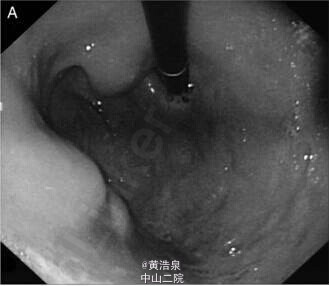

患者,男性,47 岁,消化不良、上腹部不适 2 个月,伴有体重减轻约 4kg,无消化道出血,无发热、咳嗽。既往无疾病、手术史。体格检查无明显异常。实验室检查示:血红蛋白 114g/L,血沉增快 54mm/h,无 HIV、乙肝和丙肝病毒感染。心电图、胸片无异常。 胃镜示:胃体处可见多个粘膜下肿物 (SEL)(图 1A),贲门、胃窦粘膜正常。血中嗜铬粒蛋白 A 和尿液中 5 羟基吲哚乙酸水平正常。行超声内镜检查(图 1B) 并于引导下行肿物穿刺,穿刺吸取物送检细胞学样本如图 2。 超声内镜显示胃壁内固有肌层处,可见多个大小约 1.5-2cm 界限清楚的低回声区,中心呈现高回声,伴有固有肌层的破坏 (图 1B),无胃周脏器及纵膈淋巴结累及。 穿刺吸取物细胞学检查显示为肉芽肿病变 (图 2),ZiehlNeelsen 染色示与结核分枝杆菌形态学一致 (图 3),培养后证实与染色结果一致。 超声内镜引导下肿物穿刺并送检细胞学检查及培养最终确诊为胃结核。 (来源:丁香园)